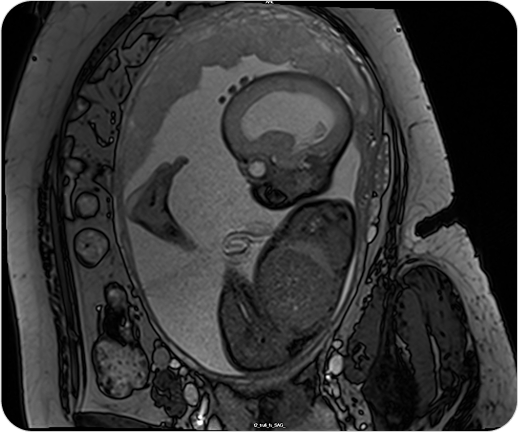

Resonancia Magnética Fetal

La resonancia fetal es un estudio no invasivo que permite observar con gran detalle el desarrollo del bebé en el útero. Es un complemento ideal de la ecografía cuando se necesita información más precisa.

La resonancia magnética fetal permite obtener imágenes detalladas del bebé durante el embarazo, sin utilizar radiación. Se utiliza como complemento del ultrasonido cuando se detectan hallazgos que requieren evaluación más precisa.

¿PARA QUE SE UTILIZA?

- Evaluar el desarrollo del sistema nervioso central fetal (cerebro y médula espinal).

- Detectar malformaciones cerebrales o anomalías estructurales.

- Valorar la anatomía de órganos internos en casos complejos.

- Confirmar o descartar hallazgos dudosos en ecografías.

- Planificar tratamientos o decisiones perinatales junto con el equipo obstétrico.

¿POR QUÉ ES UN ESTUDIO DESTACADO?

- No invasivo y seguro para la madre y el bebé.

- Alta definición de imágenes incluso en embarazos avanzados.

- Permite tomar decisiones médicas informadas y personalizadas.

- Evita resonancias post-natales.

Resonancia Magnética Fetal

La resonancia fetal es un estudio no invasivo que permite observar con gran detalle el desarrollo del bebé en el útero. Es un complemento ideal de la ecografía cuando se necesita información más precisa.

La resonancia magnética fetal permite obtener imágenes detalladas del bebé durante el embarazo, sin utilizar radiación. Se utiliza como complemento del ultrasonido cuando se detectan hallazgos que requieren evaluación más precisa.

¿PARA QUE SE UTILIZA?

- Evaluar el desarrollo del sistema nervioso central fetal (cerebro y médula espinal).

- Detectar malformaciones cerebrales o anomalías estructurales.

- Valorar la anatomía de órganos internos en casos complejos.

- Confirmar o descartar hallazgos dudosos en ecografías.

- Planificar tratamientos o decisiones perinatales junto con el equipo obstétrico.

¿POR QUÉ ES UN ESTUDIO DESTACADO?

- No invasivo y seguro para la madre y el bebé.

- Alta definición de imágenes incluso en embarazos avanzados.

- Permite tomar decisiones médicas informadas y personalizadas.

- Evita resonancias post-natales.